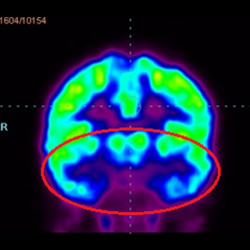

干細(xì)胞治療腦癱后改善的客觀放射學(xué)證據(jù)

細(xì)胞治療后,藍(lán)色和黑色區(qū)域減少,并且看到更活躍的區(qū)域。這表明損傷減少并改善了大腦功能。

這證明細(xì)胞療法是治療腦癱兒童安全有效的方法。細(xì)胞療法可以更新大腦損傷的核心,并且可以通過 PET CT 掃描來監(jiān)測(cè)大腦的改善情況。這些細(xì)胞療法與標(biāo)準(zhǔn)治療一起促進(jìn)腦癱兒童的生長(zhǎng)和改善。